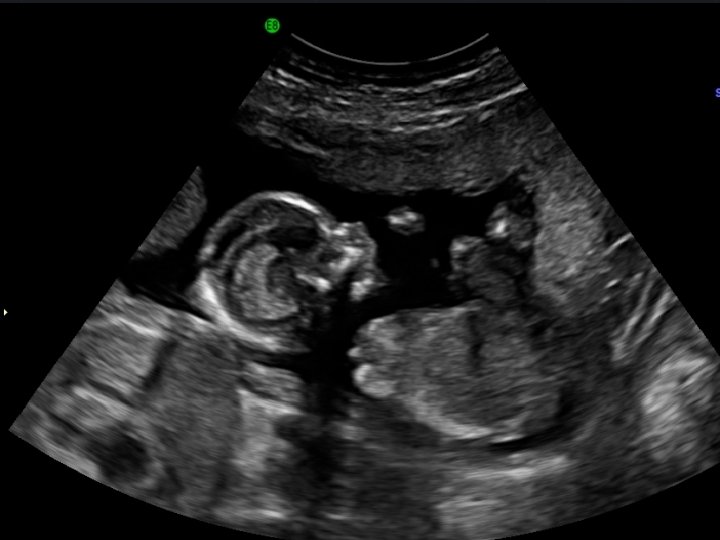

Welcome to the womb…